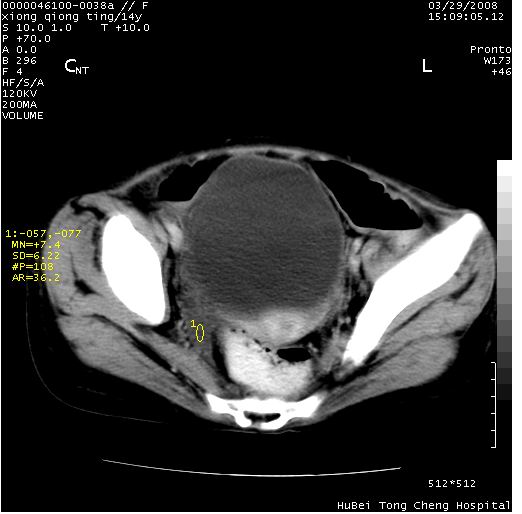

患儿 女,14岁。不规则发热一周,偶感头痛,无抽搐及呕吐。pe:神清,精神差,双侧瞳孔等大等圆,对光反射敏感,双肺未闻及明显啰音,心音有力,腹部触之似揉面感,下腹压痛,无反跳痛。

腹部b超提示:子宫缩小,盆腔积液,肝实质回声密集。

临床诊断:发热原因待查:1)腹部结核感染。2)伤寒?3)结缔组织病?

中下腹及盆腔ct轴位平扫+增强扫描(层厚10mm,螺距1.0,重建间隔10mm),图像如下:

(注:患儿检查当日上午9时口服胃肠道对比剂,下午3时许行ct扫描检查,未行对比剂直肠保留灌肠,检查当日患儿腹泻)

中下腹及盆腔ct轴位扫描(ps+ce)提示:腹部肠管明显充气扩张,并见数个不同宽度之气液平面;疑不全性肠梗阻或肠郁张。临床会诊考虑为患儿腹泻,肠郁张所致;后来未经特殊处理,患儿大便恢复正常,亦无腹胀。

临床出院诊断:1)结核性腹膜炎。2)腹膜后淋巴结结核。3)脂肪肝。